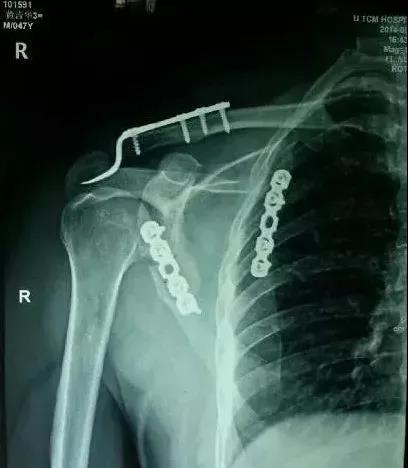

(2)肩胛带骨折

1)锁骨骨折

当骨折块伤及锁骨下动、静脉和臂丛神经时,一致认为是严重的并发症,应立即手术。

2)肩胛骨骨折

在2周之后手术,困难程度翻番。